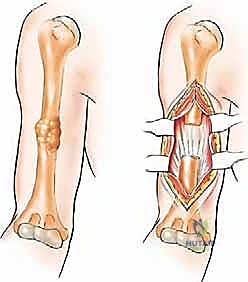

تُستخدم هذه التقنية عندما يكون هناك ورم يهدد بكسر العظم (كسر وشيك)، ولكن العظم لم ينكسر بعد، أو في حالات الكسور المرضية البسيطة.

* المسمار النخاعي التشابكي (Intramedullary Nailing): يتم إدخال سيخ معدني قوي من التيتانيوم داخل التجويف النخاعي لعظم العضد بالكامل، وتثبيته بمسامير عرضية من الأعلى والأسفل. هذه الطريقة توفر دعماً ميكانيكياً هائلاً للعظم، وتمنع الكسر، وتسمح للمريض باستخدام ذراعه فوراً.

2. الاستئصال الواسع وإعادة البناء باستخدام الإسمنت العظمي والشرائح

عندما يكون الورم قد دمر جزءاً كبيراً من جسم العضد، يتم اللجوء إلى تقنية أكثر تعقيداً:

* يتم فتح شق جراحي، وعزل الأعصاب (خاصة العصب الكعبري).

* يتم تجريف الورم بالكامل (Curettage) للوصول إلى أنسجة عظمية سليمة.

* يتم استخدام مثقاب عالي السرعة لإزالة أي خلايا سرطانية متبقية، وقد تُستخدم مواد كيميائية (مثل الفينول) أو الكي الحراري لقتل الخلايا المجهرية.

* يُملأ الفراغ العظمي الكبير بـ الإسمنت العظمي الطبي (Polymethylmethacrylate - PMMA). هذا الإسمنت لا يعوض العظم المفقود فحسب، بل إن الحرارة العالية التي يولدها أثناء تصلبه تقتل أي خلايا سرطانية متبقية.

* يتم تدعيم البناء بشريحة معدنية طويلة ومسامير قوية لضمان الاستقرار الميكانيكي.